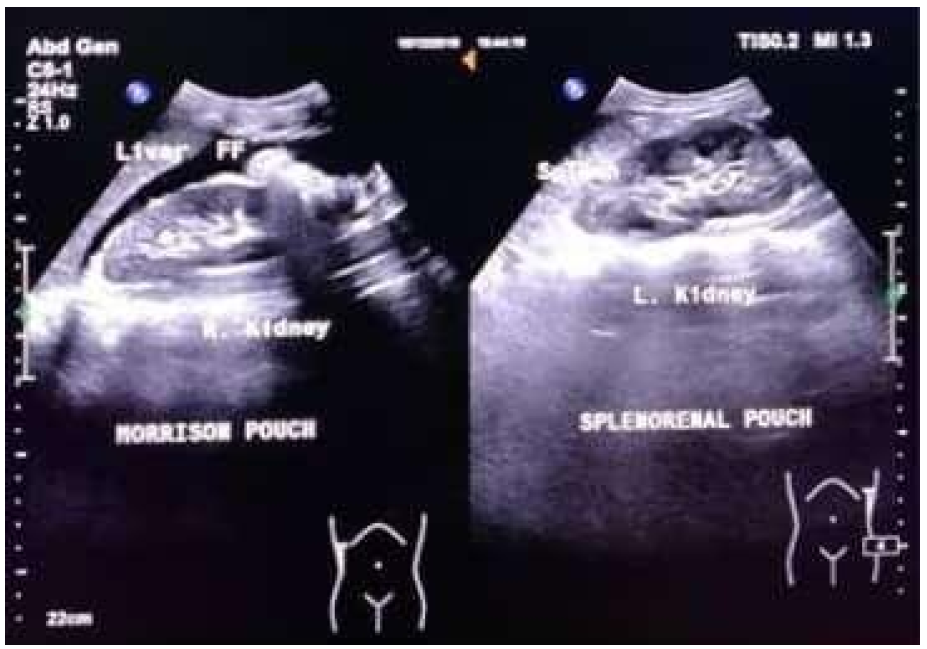

Child A, female, aged 12 years old. Twelve hours before admission to the hospital, when the patient was riding a motorcycle wearing a standard helmet, the patient had an accident colliding with another motorcycle from the opposite direction. The patient fell with her stomach hitting the road. After the incident, the patient was conscious, and the patient then complained of pain in the left side of the abdomen, headache (+), nausea (-), and vomiting (-). The rescuer took the patient to Ungaran General Hospital. The patient was infused, injected with painkillers, and treated for wounds. The family took the patient to Dr. Moewardi General Hospital Surakarta. The patient arrived at the emergency room six hours after the incident, and the pain was felt in the left abdomen. From the primary survey examination, the airway was still free with normal breathing, RR 20 x/m, no circulatory disturbances, BP 110/70 mmHg, HR 98 x/min with GCS E4V5M6, isochor pupil (3mm/3mm), pupillary light reflex (+/+), lateralization (-/-), and a temperature of 36.8 degrees Celsius. In the secondary survey, injuries were found in the left hypochondria region, no open wounds, no abdominal distension, bowel movements (+), and pain when palpated in the left upper quadrant of the abdomen. In stable hemodynamic conditions, the FAST examination was performed, and FAST (+) was obtained in Morrison's pouch and splenorenal (Figure 1).

Figure 1: FAST Examination (+) on the Morrison Pouch and Splenorenal Pouch

In this case, the patient showed FAST (+) in the Morison Pouch and minimal (+) in the Splenorenal Pouch. The FAST ultrasound results were then followed by a contrast CT scan of the abdomen, and spleen rupture grade IV and free intra-abdominal fluid were obtained. In this case, the result (+) in the Morison Pouch was not accompanied by liver rupture.